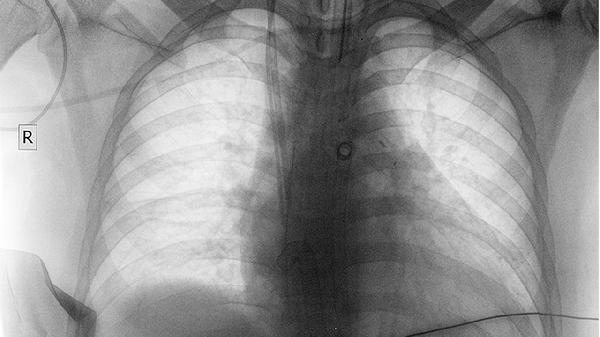

需要明确的是,肺癌的治疗效果受多种因素影响,包括病理类型、分期、基因突变状态等。单纯依靠安康欣胶囊难以达到理想的治疗效果。中晚期肺癌患者更需优先考虑靶向治疗、免疫治疗等现代医学手段。该药物使用过程中可能出现胃肠道不适等不良反应,与其他抗肿瘤药物联用时更需谨慎评估。